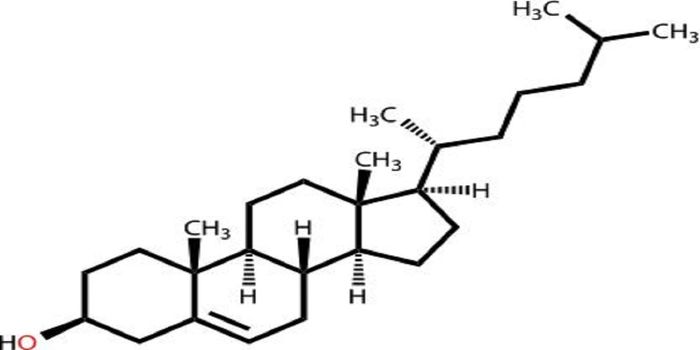

JUL 18, 2017CancerStatins are often prescribed to help lower cholesterol levels, especially for patients at high risk for coronary heart d ...